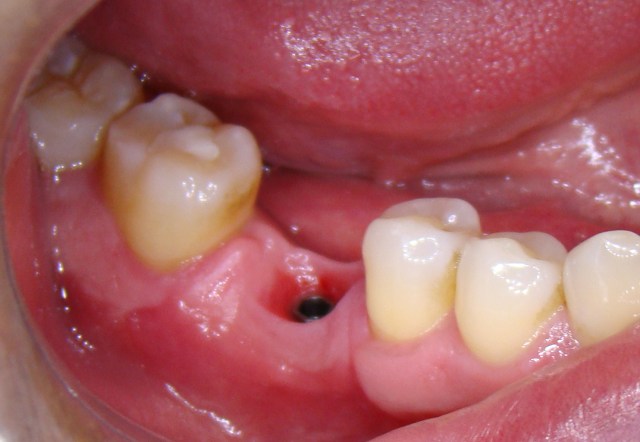

Paciente apresentava uma ausência do elemento 46 (primeiro molar inferior) e queixava-se d...